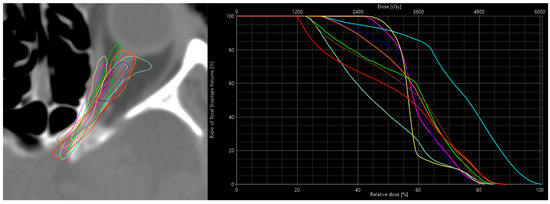

3.1. Results for Sensitivity

| ONL Contour | Calc. Dose | Pred. Dose | Δ Dose Calc-Pred | DSC | Δ to Calc-Ref | Δ to Pred-Ref |

|---|---|---|---|---|---|---|

| Reference | 34.7 | 35.5 | −0.8 | n.a. | n.a. | n.a |

| Alternative-1 | 32.2 | 35.7 | −3.5 | 0.31 | −2.5 | 0.2 |

| Alternative-2 | 30.7 | 32.4 | −1.7 | 0.26 | −4 | −3.1 |

| Alternative-3 | 34.2 | 34.5 | −0.3 | 0.63 | −0.5 | −1 |

| Alternative-4 | 31.8 | 34.1 | −2.3 | 0.59 | −2.9 | −1.4 |

| Alternative-5 | 26.9 | 30.1 | −3.2 | 0.51 | −7.8 | −5.4 |

| Alternative-6 | 32.8 | 36 | −3.2 | 0.20 | −1.9 | 0.5 |

| Alternative-7 | 41.8 | 41.2 | 0.6 | 0.16 | 7.1 | 5.7 |

| Alternative-8 | 35.3 | 33.1 | 2.2 | 0.58 | 0.6 | −2.4 |

| Alternative-9 | 34.5 | 36.1 | −1.6 | 0.05 | −0.2 | 0.6 |

| Mean | 33.49 | 34.87 | −1.38 | 0.37 | Corr. Coeff.: 0.89 | |